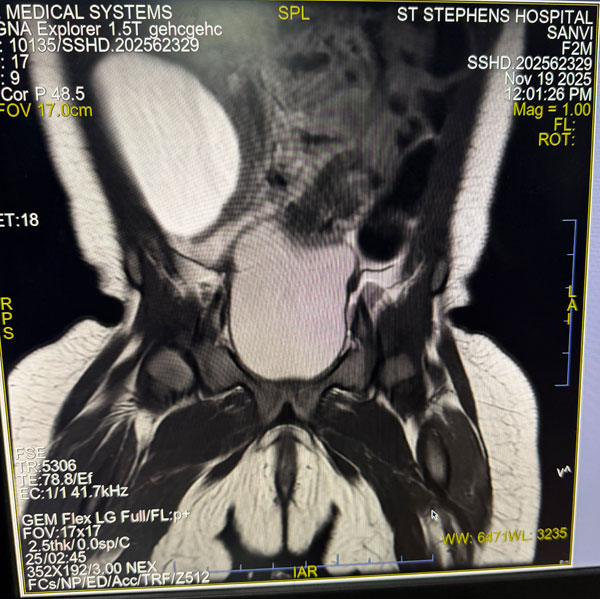

The patient was diagnosed antenatally with a large intra-abdominal cyst. Postnatal evaluation via Ultrasound and MRI identified a significant cystic mass in the right lumbar region, distinctly separate from the right ovary.

We proceeded with a Diagnostic Laparoscopy, which revealed a surprising anatomical finding. The mass was actually the left ovary, which had transformed into a large cyst and underwent torsion on its pedicle. Due to its size and the inherent mobility of the neonatal adnexa, it had migrated across the midline to the right lumbar region.